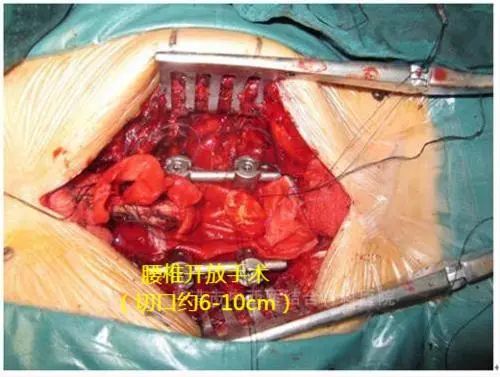

微创手术与开放手术切口对比